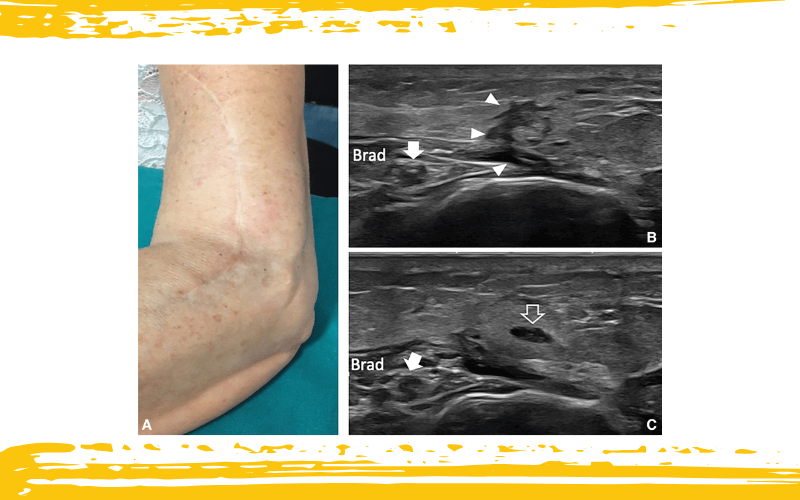

Lesión traumática del nervio cutáneo posterior del antebrazo (PCNF).

A. Una fotografía del miembro superior muestra una cicatriz extensa en la cara lateral del brazo distal y antebrazo proximal, siguiendo el trayecto del nervio cutáneo posterior del antebrazo (PCNF). El paciente refiere disminución de la sensibilidad alrededor de la cicatriz y dolor paroxístico al roce ligero en la misma zona, tras un traumatismo penetrante sufrido 2 meses antes.

B. La imagen ecográfica muestra una cicatriz (puntas de flecha) que afecta al tejido subcutáneo alrededor del septo intermuscular lateral, respetando el nervio radial (flecha), el cual discurre distal al septo y se encuentra protegido por el músculo braquiorradial (BRad).

C. Una imagen ecográfica obtenida inmediatamente distal a la cicatriz revela cambios edematosos en el tejido subcutáneo, junto con un neuroma traumático que afecta al nervio cutáneo posterior del antebrazo (PABCN, flecha delineada).